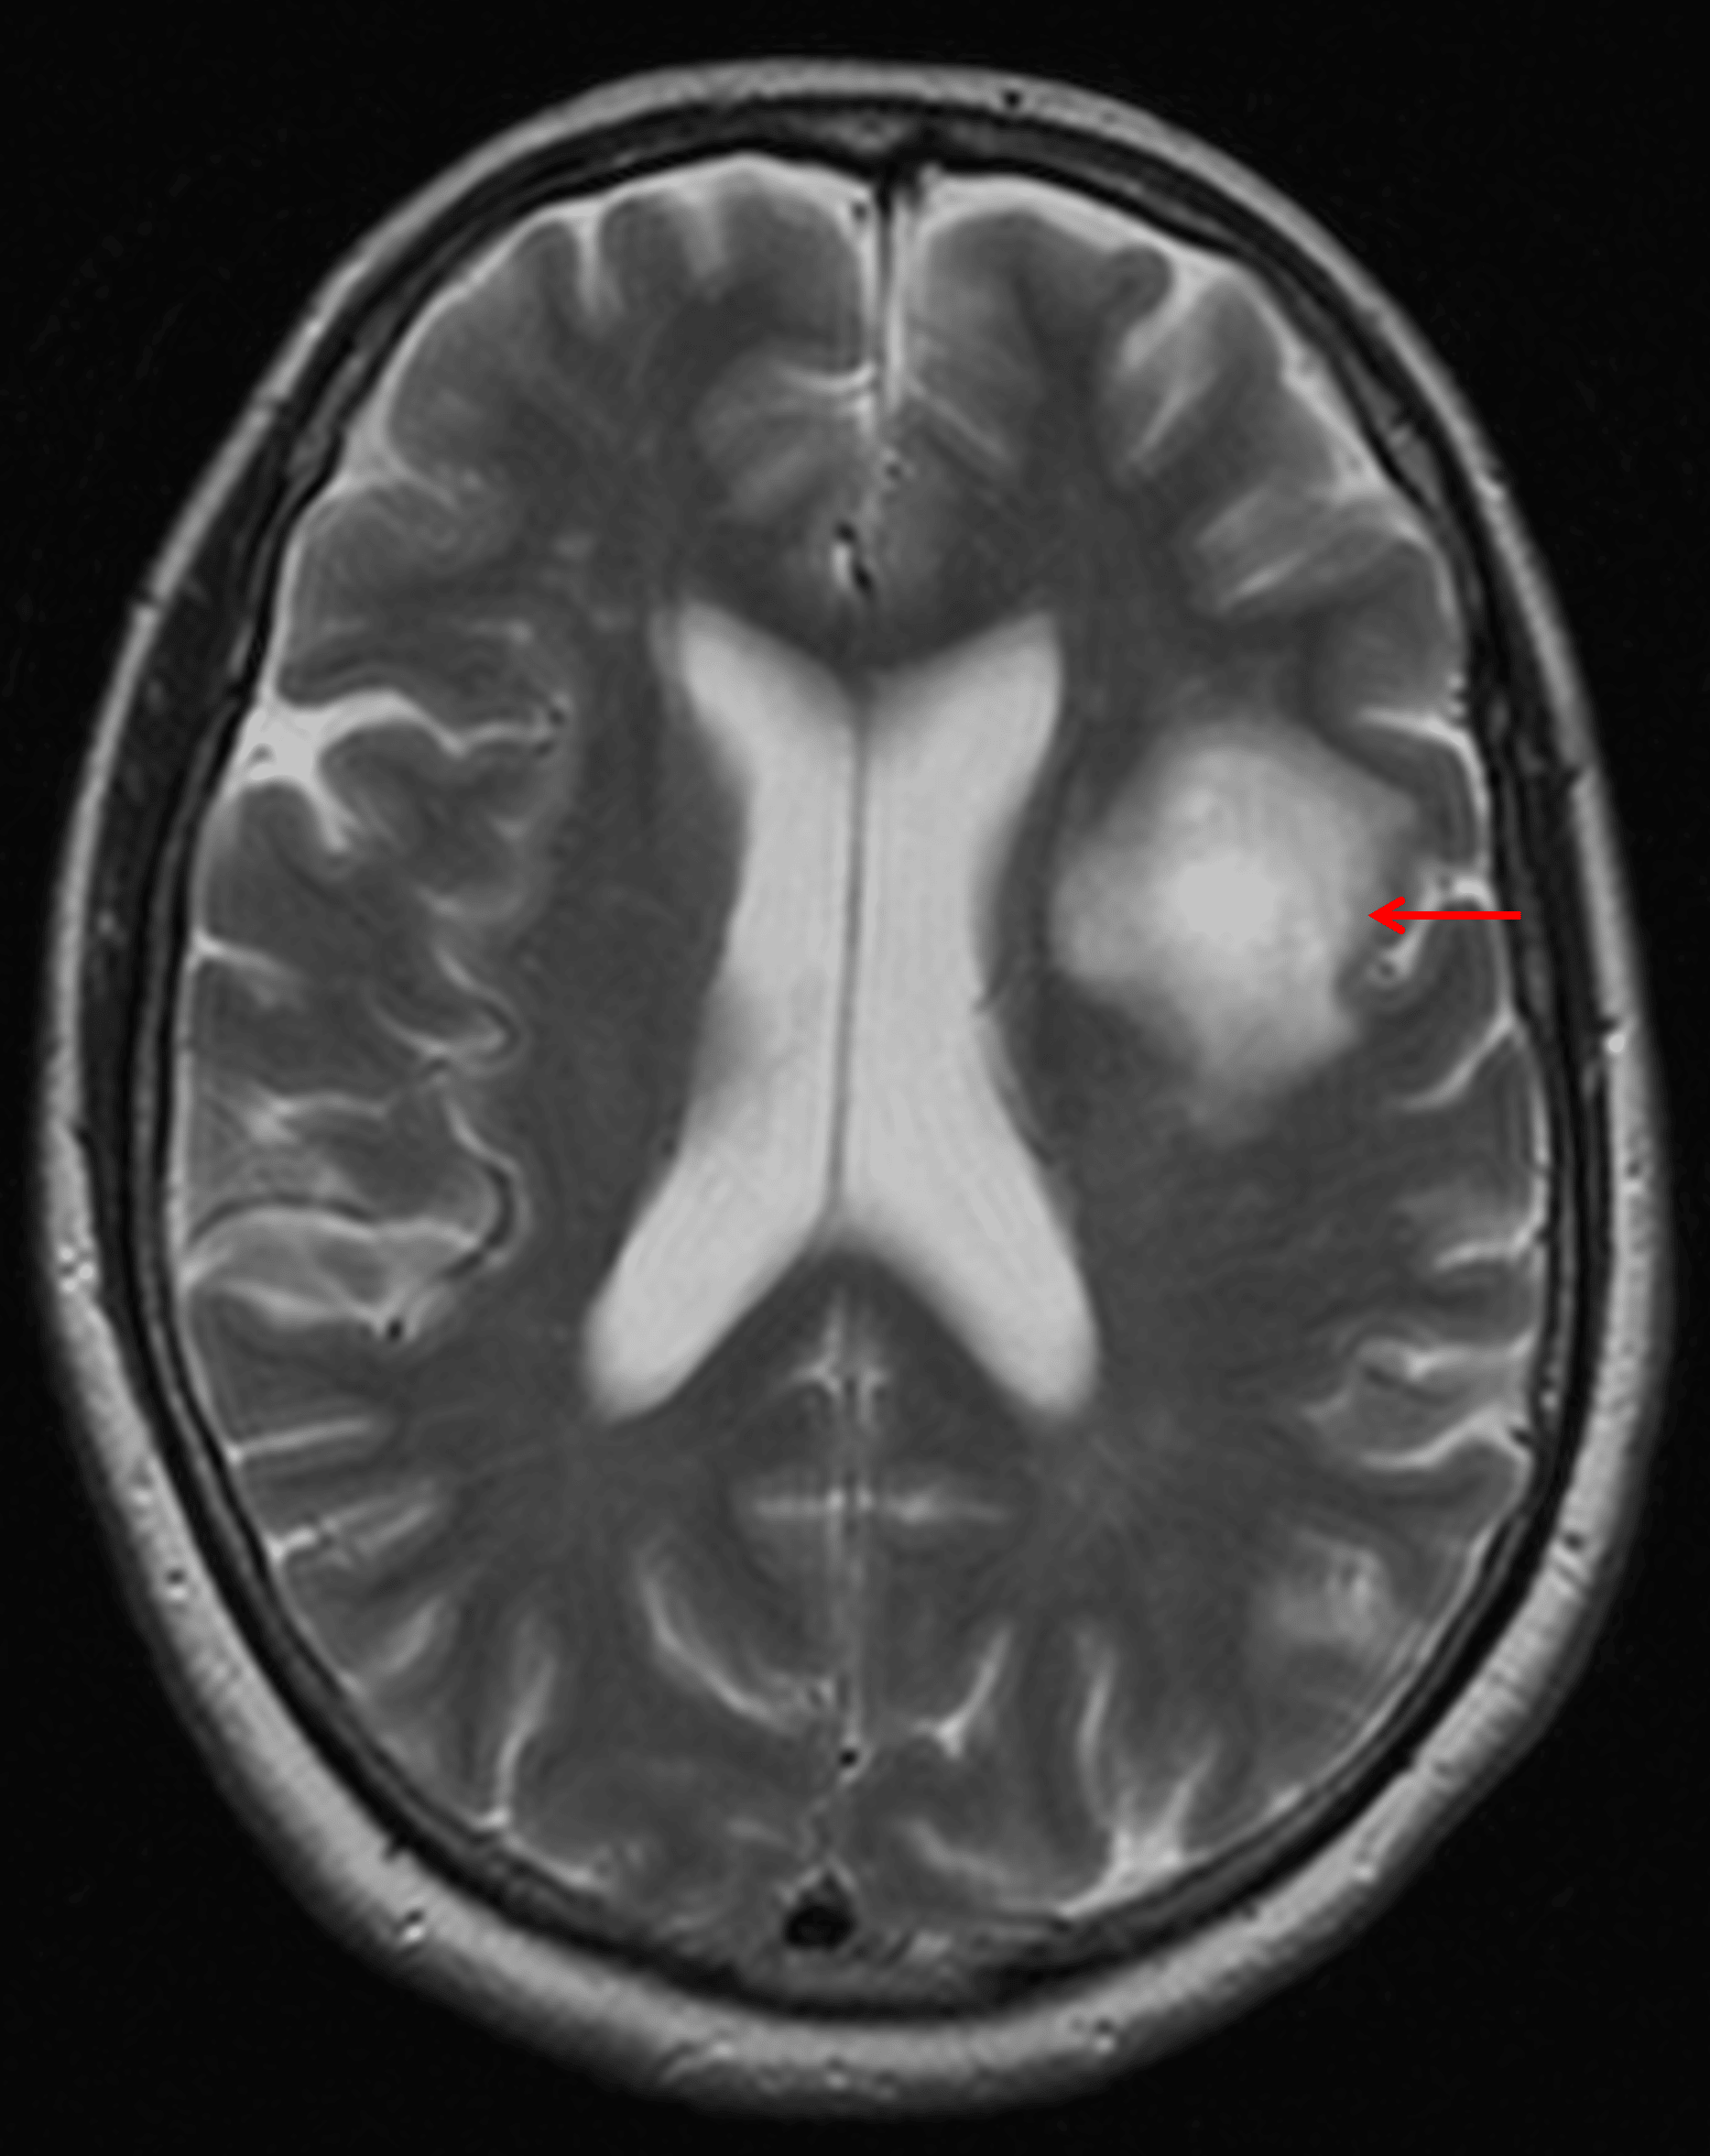

Masslike area of T2 signal hyperintensity in the left frontal white matter (red arrow) with surprisingly essentially no mass effect on the left lateral ventricle or adjacent sulci.

Tumefactive demyelinating lesion